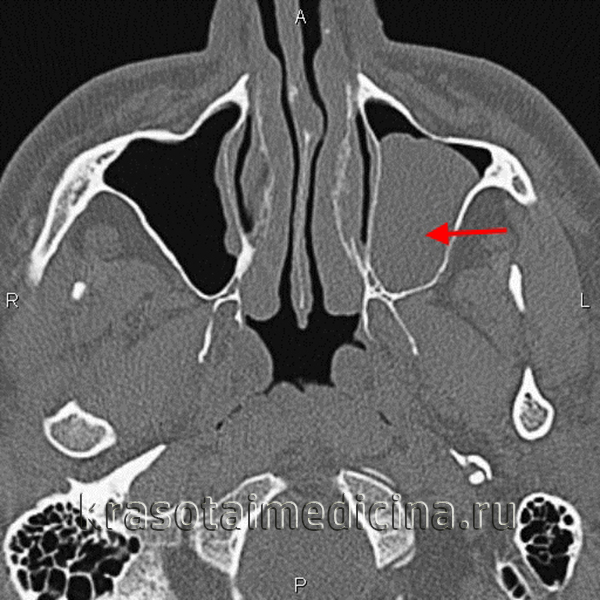

(Слева) На периапикальной рентгенограмме задних отделов верхней челюсти справа, не содержащей зубов, на фоне воздуха визуализируется куполообразное затемнение в верхнечелюстной пазухе. Край пазухи возле затемнения интактен. Обратите внимание на наложение скулового отростка.

(Справа) На корональной КЛКТ (реконструкция) визуализируется куполообразная ретенционная псевдокиста в правой верхнечелюстной пазухе. Кортикальная пластинка на периферии псведокисты отсутствует, края пазухи интактны.

(Справа) На аксиальной КЛКТ (реконструкция) визуализируется муцинозная ретенционная псевдокиста, занимающая всю камеру правой верхнечелюстной пазухи на этом уровне. Важно не спутать перегородку в пазухе с кортикальной пластинкой на периферии образования. Обратите внимание на утолщение слизистой оболочки камер левой верхнечелюстной пазухи. (Слева) На периапикальной рентгенограмме задних отделов верхней челюсти справа, не содержащей зубов, на фоне воздуха визуализируется куполообразное затемнение в верхнечелюстной пазухе. Край пазухи возле затемнения интактен. Обратите внимание на наложение скулового отростка.